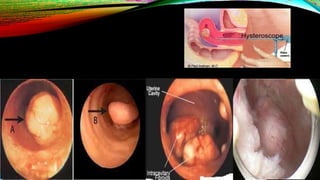

• Hysteroscopy — Diagnostic hysteroscopy is useful for visualizing the

endometrial cavity.

• Similar to saline infusion sonography, this allows evaluation for submucosal

or protruding myometrial fibroids and can characterize the extent of

protrusion.

• This can be performed in the office or operating room

• Hysteroscopy —Diagnostic hysteroscopy is useful for visualizing the endometrial cavity. • Similar to saline infusion sonography, this allows evaluation for submucosal or protruding myometrial fibroids and can characterize the extent of protrusion. • This can be performed in the office or operating room